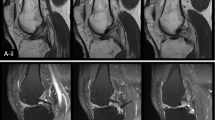

The ACL and PCL were segmented manually on the high spatial resolution anatomical 3D-FS SPGR images using ITK-SNAP v 3.6.0 [22]. Segmentation was performed by a single reader (CDSR) and supervised by a musculoskeletal radiologist with 8 years’ experience (JWM). Segmentations were repeated by the same reader at a second timepoint (at least 2 weeks following the initial segmentation) to assess intra-rater reproducibility, and also by an independent second reader, a radiologist with 3 years’ experience (VC), to assess inter-rater reproducibility. Segmentation was done on 5–10 sagittal images corresponding to 2–3 images on T1rho/T2 maps. An example of a 3D- rendering made from a segmentation in ITK-SNAP is shown in Fig. 1.